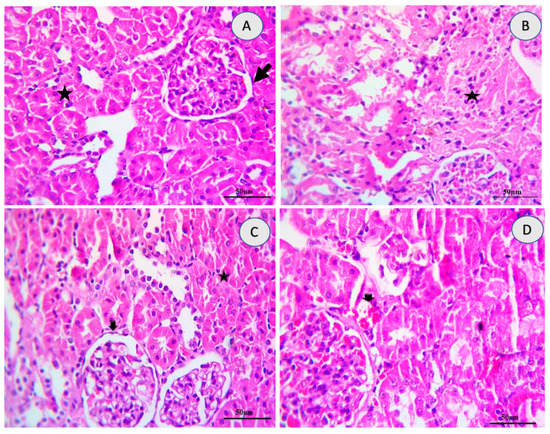

2.5. Renal Histology

| Lesions | Control | 10-DHGD | Tramadol | Tramadol+10-DHGD |

|---|---|---|---|---|

| Inflammation (nephritis) | 0 | 0 | 2 | 0 |

| Necrosis/Degeneration | 0 | 0 | 3 | 1 |

| Hemorrhages | 0 | 0 | 3 | 1 |

| Cystic Dilatation | 0 | 0 | 1 | 0 |

| Fibrosis | 0 | 0 | 1 | 0 |

| Edema | 0 | 0 | 2 | 0 |

| Tubular Casts | 0 | 0 | 3 | 0 |